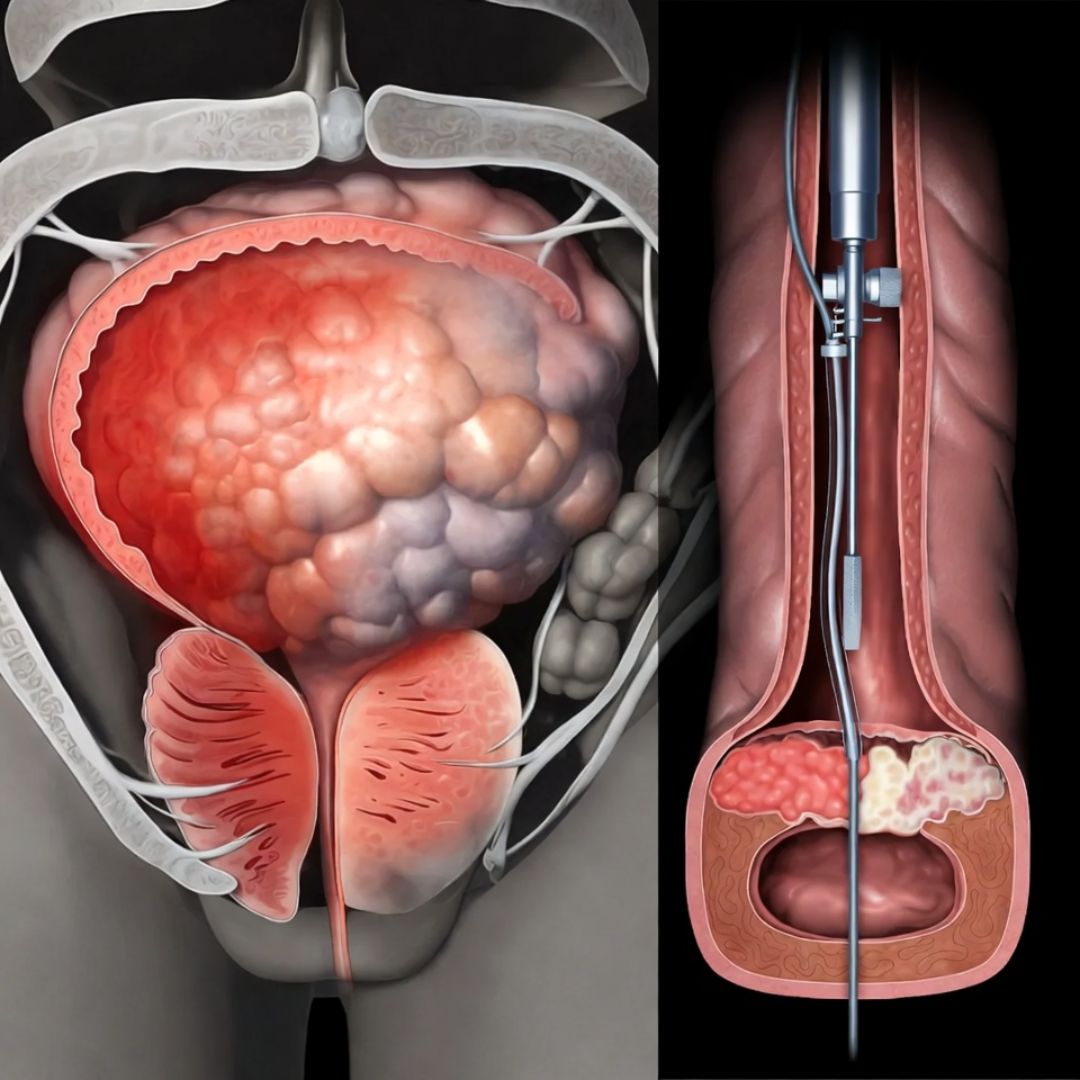

Running from the base of your spinal cord, through your pelvic region, and into the erectile tissue of the penis, there is a set of nerve fibres called the cavernous nerves.

That signal travels down through the spinal cord, passes through a nerve relay point in the pelvis called the pelvic plexus, and then travels along the cavernous nerves directly into the smooth muscle tissue lining the corpora cavernosa — the two chambers inside the penis that fill with blood during erection.

When the muscle relaxes, the internal blood vessels dilate. Blood rushes into the chambers. The penis becomes erect.

This is what happens in the cavernous nerve network of the majority of men who develop progressive erectile dysfunction after the age of 50:

The protective myelin sheath that insulates the cavernous nerve fibres begins to degrade.

This process — called progressive cavernous nerve demyelination — is silent, cumulative, and slow.

The cavernous nerves do not travel through the body in isolation.

They pass in close anatomical proximity to the prostate gland — running alongside it on either side as they make their way from the pelvic plexus to the erectile tissue.

Sustained prostate inflammation causes swelling in the tissue immediately surrounding the cavernous nerve bundles.

That swelling creates chronic pressure on the nerves — not acutely painful, but sufficient, over months and years, to cause compression-related damage to the myelin sheath.

For men who have undergone prostate surgery — whether for benign prostatic hyperplasia or for cancer — the situation is more direct.

The cavernous nerves are frequently damaged during prostatic procedures, sometimes unavoidably given their anatomical position.